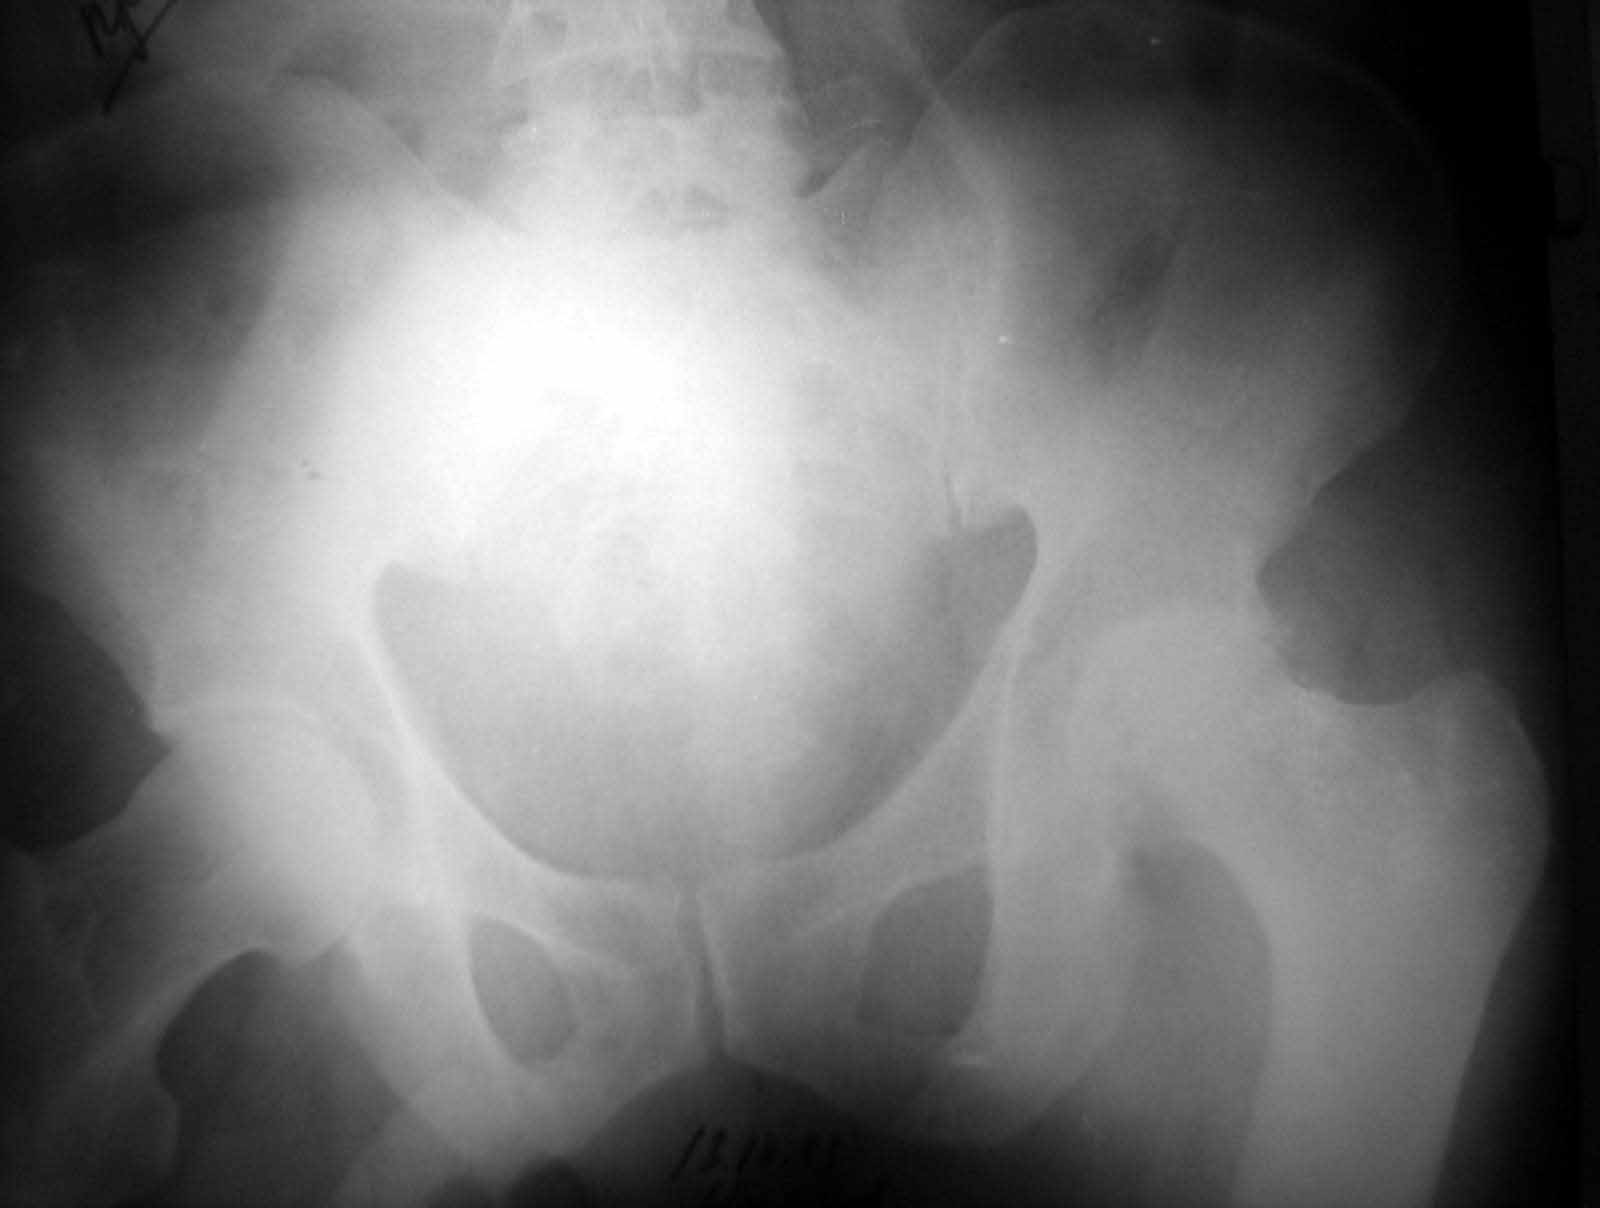

Больной Н. 54 лет. Поступил в подвздошным вывихом левого бедра. После попытки закрытого одномомендного вправления 2 мес. на скелетном вытяжении. На Rg контроле видимость вправления, на КТ - неустраненный вывих. По причине тяжелой соматической патологии открытое вправление и репозицию заднего края выполнить не представляется возможным. Вправление аппаратом внешней фиксации, КТ - этапах вправления - дефект заднего края. Что вы нам посоветуете по дальнейшей тактике? Больной Н. 54 лет. Диагноз: Закрытый оскольчатый перелом заднего края вертлужной впадины слева, подвздошный вывих левого бедра. Ушиб грудной клетки. ИБС. Стенокардия напряжения. ФКI-II. Постинфарктный кардиосклероз. Артериальная гипертония II степени, риск IV. НI. Состояние после аорто-коронарного шунтирования. Хронический бронхит. ДНI.Травма в результате ДТП. Больной лечился консервативно - закрытое одномоментное ручное вправление, фиксация скелетным вытяжением в течение 2 месяцев. На контрольных обзорных рентгенограммах таза в динамике: головка бедра располагается в проекции вертлужной впадины, суставные поверхности конгруентны. После снятия скелетного вытяжения выполнялся КТ - контроль тазобедренного сустава, на котором обнаружен неустраненный задний вывих бедра. Через 2 месяца наложена передняя тазовая и бедренная опоры. По причине тяжелого соматического состояния не представлялось возможным выполнить открытое вправление вывиха и остеосинтез заднего края. Представлен КТ- контроль на этапе вправления, на котором виден дефект заднего края вертлужной впадины.

Я не понял как отправлять несколько файлов для графического приложения. Отправляю прямую проекцию в день травмы, после "вправления" на вытяжении и КТ. На данный момент головка бедра во впадине. КТ во вправленном состоянии отправлю по возвращении